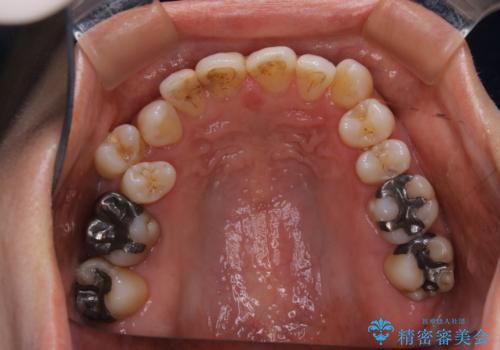

- 右上の小臼歯が二本とも90度捻じれてしまっており、奥歯の噛み合わせに問題が生じていました。

今回は右上の奥歯に入っていた銀歯の形が悪く、そのせいで歯を並べるスペースが足りない状態でした。

右上の歯の被せ物を作りなおし、適切な歯の大きさに代えてあげることによってスペースを作りました。

また、それだけではスペースが足りない為右上の奥歯は遠心移動を行っています。